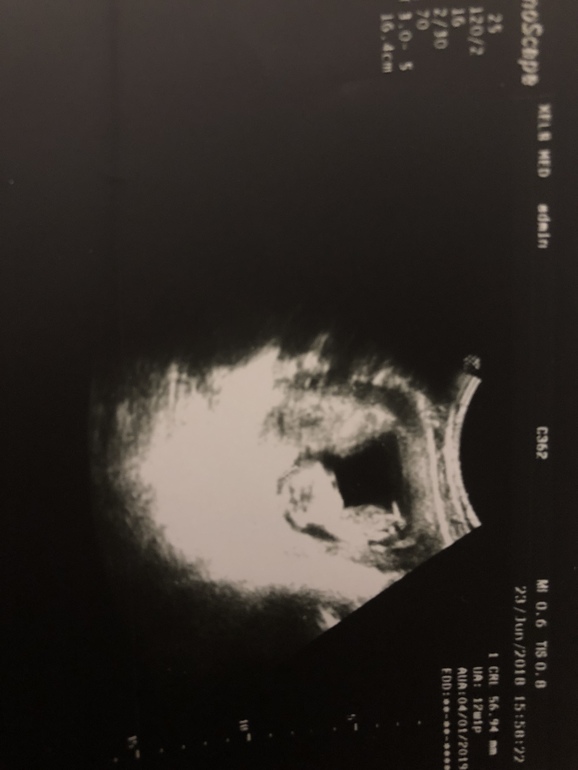

В первом триместре я успела сбегать на 5 узи, вместе с 1 скринингом)) В 12,1 неделю червячек оформился во вполне человеческий головастенький эмбриончик 😍

Это наше единственное фото в полный рост и размер за всю беременность 🤦🏻♀️))

И, внимание, на том же сроке моя врач-орлинный глаз с 80% вероятностью нагадала нам мальчика!! Забегая вперёд сообщу, что она оказалась полностью права 👍🏻👍🏻.